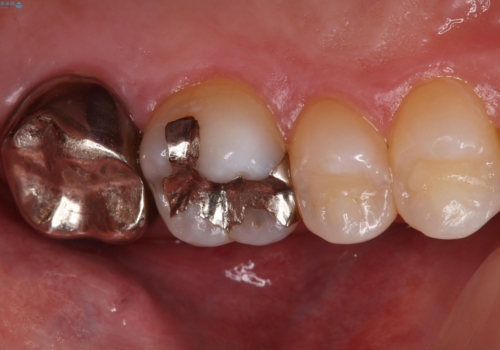

- 歯茎がよく腫れ、痛みが出ることを主訴に来院された患者様です。

レントゲン等から、金属の被せ物が歯にあって作られていないことがわかり、汚れの貯留もみられました。

金属を除去し、虫歯の治療後に型取りを行い、清掃性、審美性に優れたセラミックインレー、セラミッククラウンを装着いたしました。